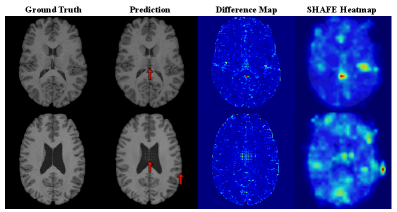

4.2 Validation of Generated Hallucinations

Figure 3 shows intrinsic and extrinsic hallucinations generated by HalluGen. The images appear realistic, altering tissue morphology such as sulci and ventricles. A key trend emerges: intrinsic hallucinations often cause morphological distortions (shape or size), whereas extrinsic ones introduce new plausible structures, leading to topological changes.

We validate HalluGen’s taxonomy compliance in Tab. 2 by measuring measurement- and image-space deviations within masked regions. Intrinsic hallucinations exhibit measurement loss roughly 7 times higher than DPS, confirming violation of measurement consistency. Extrinsic hallucinations retain low measurement loss but diverge in image space, consistent with the formal taxonomy (Eq. 2–3). Fig. 3 further visualizes measurement-space difference maps, with extrinsic cases showing much lower errors than intrinsic ones within hallucinated regions.